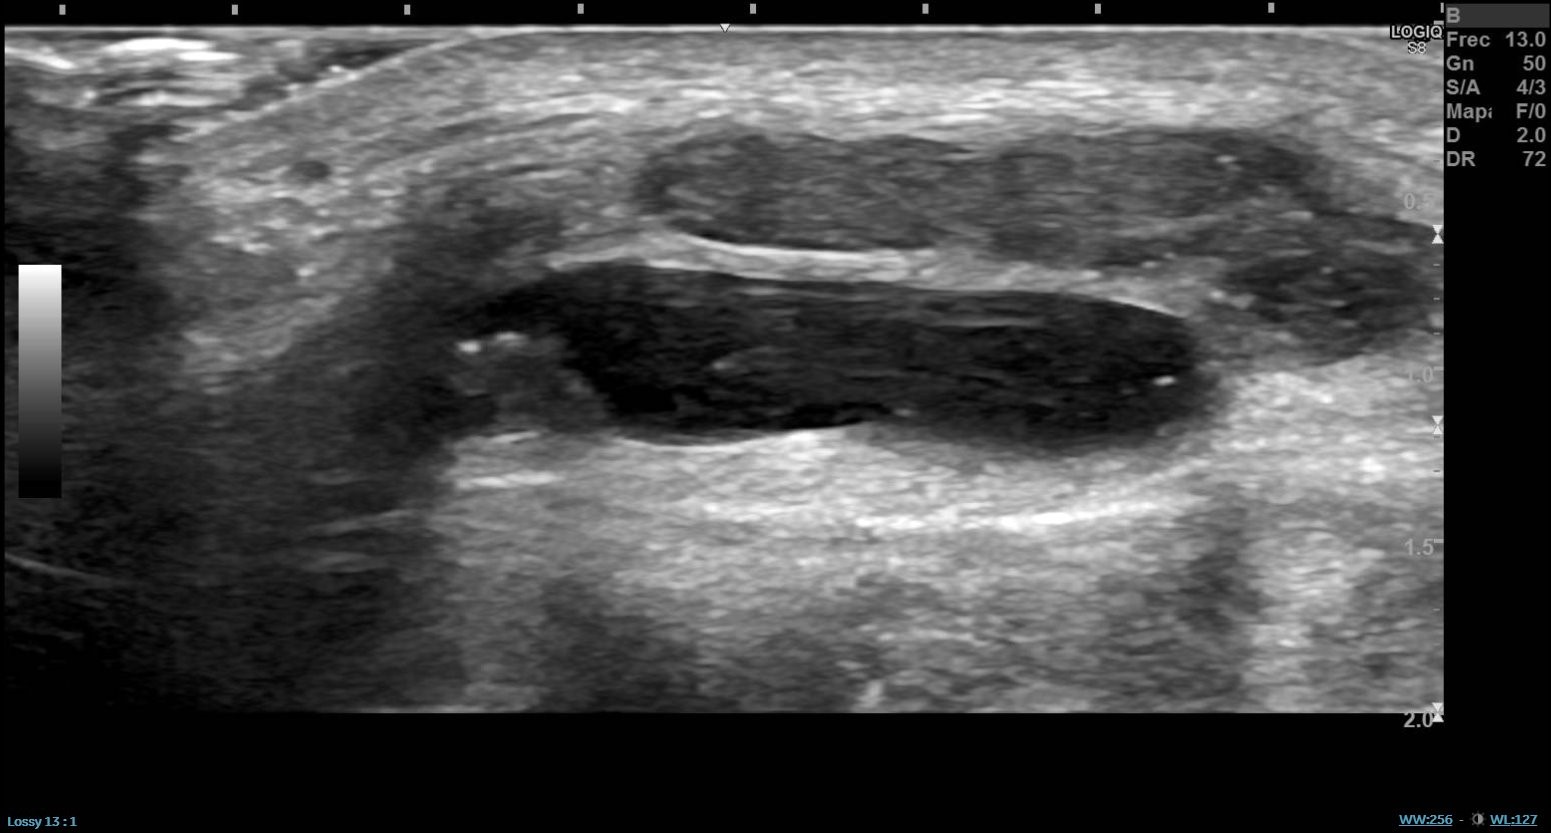

Ecografía con sonda lineal cara externa rodilla izquierda: lesión subcutánea quística poliglobulada, superior al margen más externo del compartimento femorotibial. No se ve pedículo hacia dicho especio articular ni hacia la articulación tibioperonea superior sin que se pueda descartar que no se trate de un ganglión. No hay datos de rotura del margen externo del menisco lateral sin poder descartar un quiste parameniscal.

Se recomienda resonancia magnética nuclear (RMN) para confirmar diagnóstico.